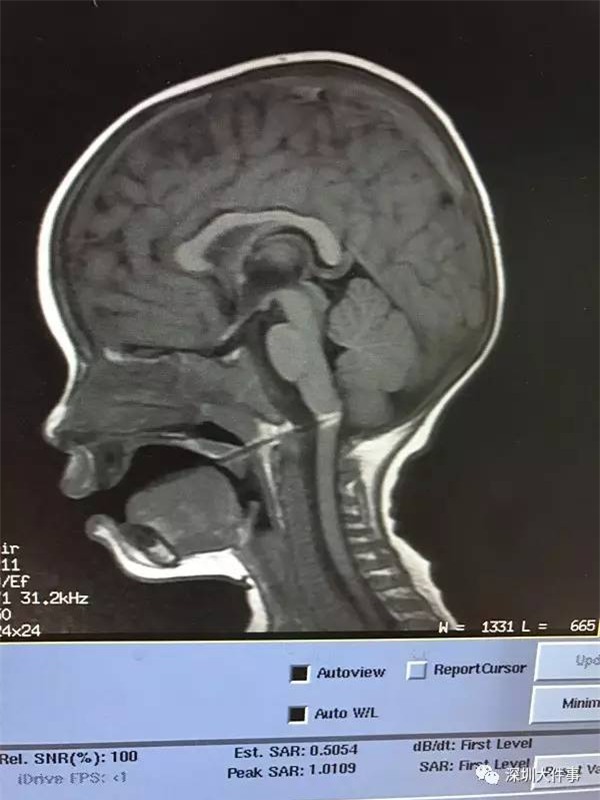

Hình chụp X-quang thấy được cây xiên que đã đâm vào hành não của cậu bé. (Ảnh: Sohu)

Theo như thông tin của bệnh viện thu thập được, cậu bé 1 tuổi đang bắt đầu chập chững biết đi. Người nhà bất cẩn đưa cho cậu bé cây xiên que xúc xích để ăn, do đứng không vững nên đã té xuống, vô tình khiến cây xiên que đâm thẳng vào cổ họng. Ngay lập tức, người nhà đưa cậu vào cấp cứu và chụp X-quang. Hình ảnh cho thấy, cây xiên que đã đâm vào hành não và cậu bé đang trong tình trạng vô cùng nguy kịch.